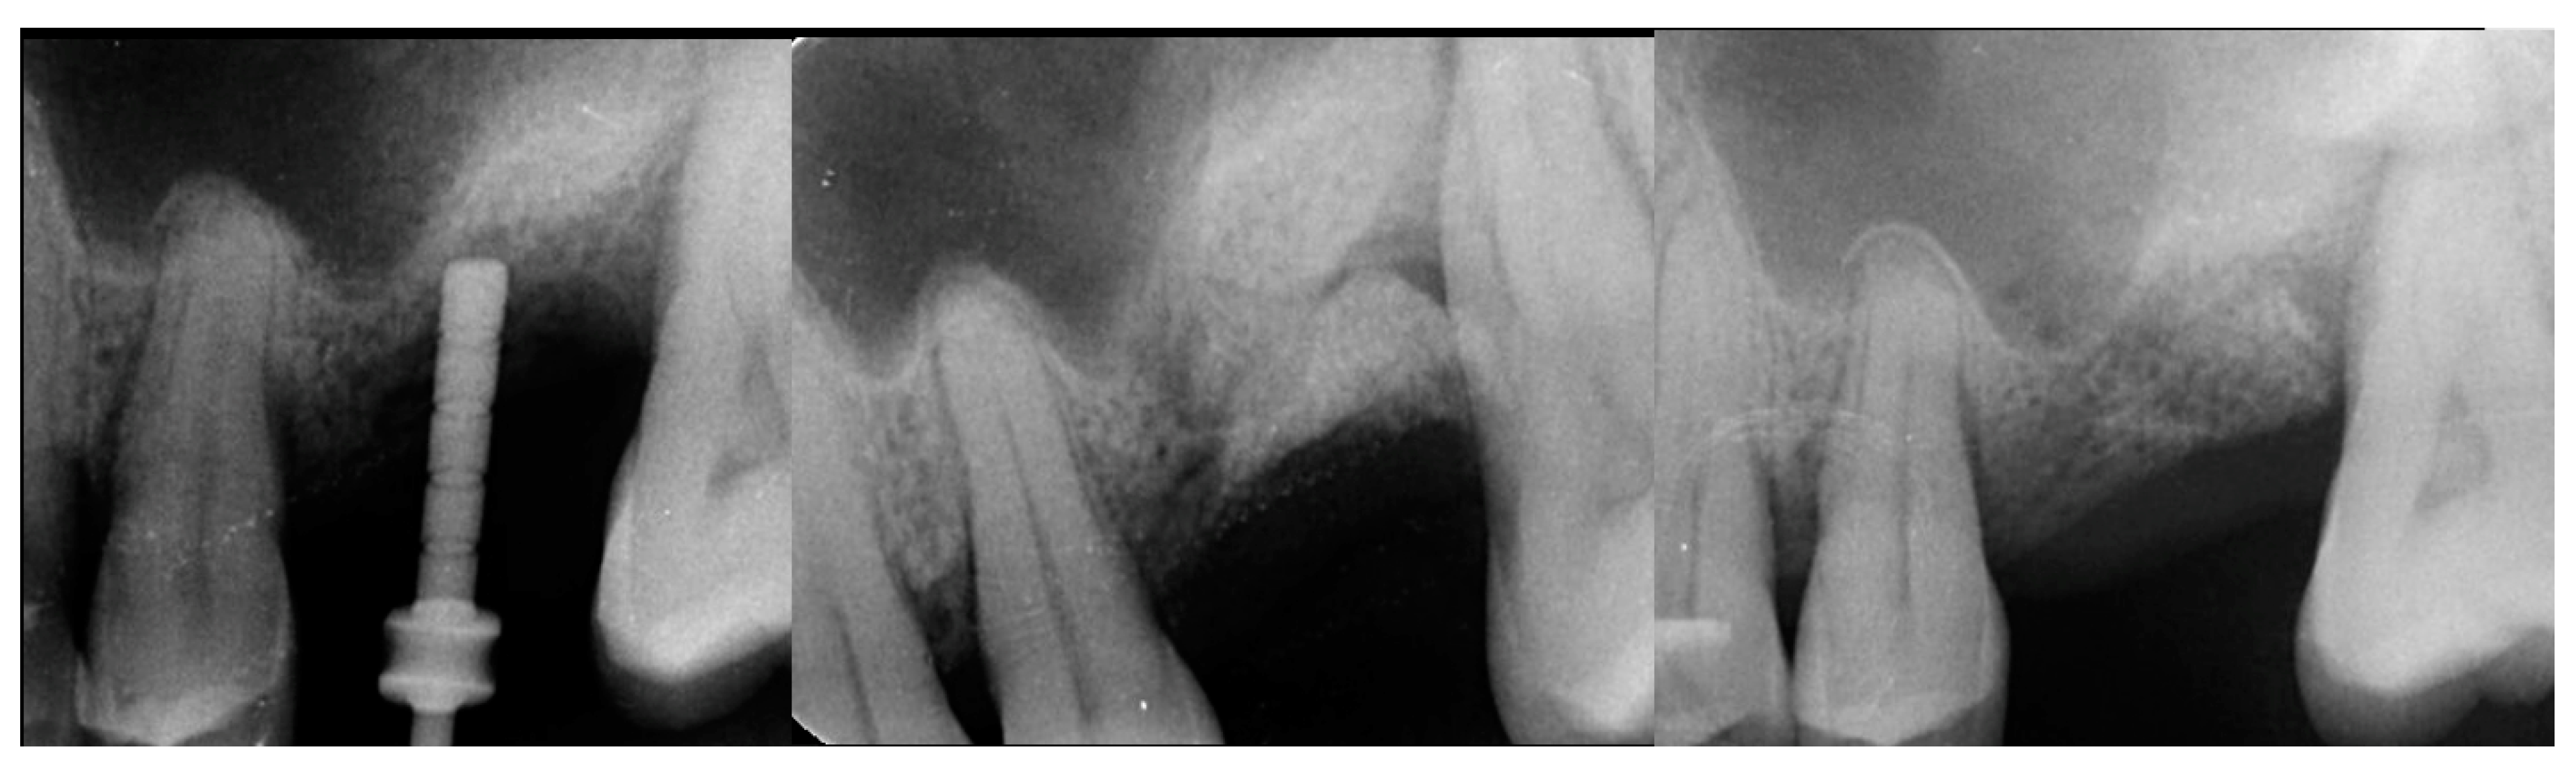

A 54-year-old female patient presented with loss of crowns on the upper left 1st and 2nd maxillary molars that had previous endodontic treatment. Examination noted minimal coronal tooth structure remaining and significant bone loss between the two molars with probing of over 10 mm. A periapical radiograph was obtained and confirmation of the poor condition of the two molars both structurally and periodontally was noted (Figure 1, left). Treatment options were discussed with the patient who wished a fixed approach. It was recommended that the two failing molars be extracted, and socket grafting be performed to create a crestal base to support an implant following site healing. At a subsequent surgery, a crestal sinus augmentation would be performed with simultaneous implant placement. This would then be allowed to heal before restoration of the implant at the 1st molar site was initiated.

Figure 1.

Failing endodontically treated 1st and 2nd molars (left), socket grafting with EthOss at time of extraction (middle) and following 10 weeks of healing demonstrating increased ridge height for implant placement with simultaneous crestal sinus augmentation (right).

The consent form was reviewed with the patient and then signed. Local anesthetic was administered into the buccal vestibule adjacent to the molars to be treated. The two molars were atraumatically extracted, and the sockets were curetted to remove any residual tissue. The EthOss graft material syringe was held vertically and per the manufacturer’s instructions, sterile saline was added to the syringe to wet the graft material. Once the saline had wetted the graft material, the end cap was removed from the syringe and a piece of dry gauze was utilized to remove any excess saline. The syringe was then carried to the intraoral site and expressed into the sockets. The material was gently compressed to shape it to fill the void being grafted with sterile gauze for 3 min at which stage it began to harden, showing resistance to pressure and being firm to touch. The flap margins were then closed to achieve primary closure and secured with 5–0 PGA sutured in an interrupted fashion. A periapical radiograph was obtained to document the socket grafting (Figure 1, middle).

The patient returned at 10 weeks post-surgery and a periapical radiograph was obtained to evaluate the graft healing (Figure 1, right). The graft was noted to have blended with the surrounding host bone and was deemed ready for implant placement. The soft tissue covering the grafted portion of the ridge was keratinized and no inflammation was noted (Figure 2). Local anesthetic was again administered in a similar manner as the previous surgery. A crestal incision was made from the distal of the distal papilla at the 2nd premolar to a point where the 1st molar would be positioned. A releasing incision was made at the distal of the papilla and also at the posterior extent of the crestal incision and extended into the buccal vestibule. A full-thickness flap was elevated to expose the crestal ridge (Figure 3). The graft had converted to bone at the extraction sockets. A pilot drill was utilized to start the osteotomy to a depth of 4 mm, 2 mm shy of the sinus floor as measured on the radiograph. The osteotomy was increased laterally utilizing Densah osseodensification burs (Versah, Jackson, MI, USA) to a width of 4 mm (Figure 4, left). EthOss graft material that had been hydrated in the syringe was dispensed into the osteotomy and the final Densah bur was utilized to elevate the sinus floor and laterally spread the graft material to gain height for the implant placement (Figure 4, right). A 5 mm × 8 mm Paltop Addvanced (Paltop, Cesarea, Israel) implant was introduced into the site to the desired crestal depth (Figure 5, left). A cover screw was placed, and additional EthOss graft material was placed at the crest to fill a depression on the distal aspect adjacent to the implant (Figure 5, middle). A periapical radiograph was obtained to document the implant and associated sinus/crestal grafting performed at this stage (Figure 5, right).